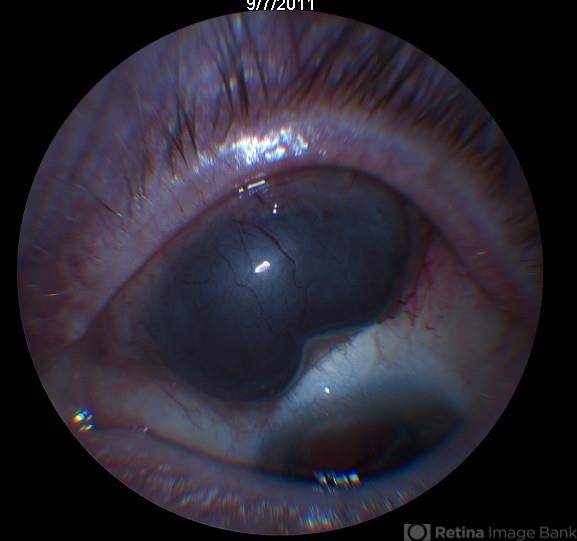

- ciliary body mass

- Patient presented with mass hidden by upper lid, 20/30 vision